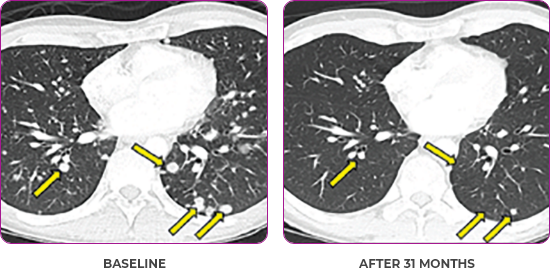

BASELINE

AFTER 31 MONTHS

PATIENT CASE:

METASTATIC, RAIa-REFRACTORY,

PAPILLARY THYROID CANCER1,2

- 33-year-old male

- Progression on RAI and first line systemic therapy

- PRa after 2 cycles of VITRAKVI® (larotrectinib)

- Confirmed partial response on VITRAKVI lasting 55 cycles

Response to VITRAKVI1,2

- Confirmed partial response (92.6% reduction in target lesions)

- Treatment continued for 55 cycles

- VITRAKVI was well tolerated; patient did not have to discontinue due to AEa

- No treatment interruptions or dose reductions

Response in primary and metastatic lesions1

Images courtesy of Dr Steven Waguespack.